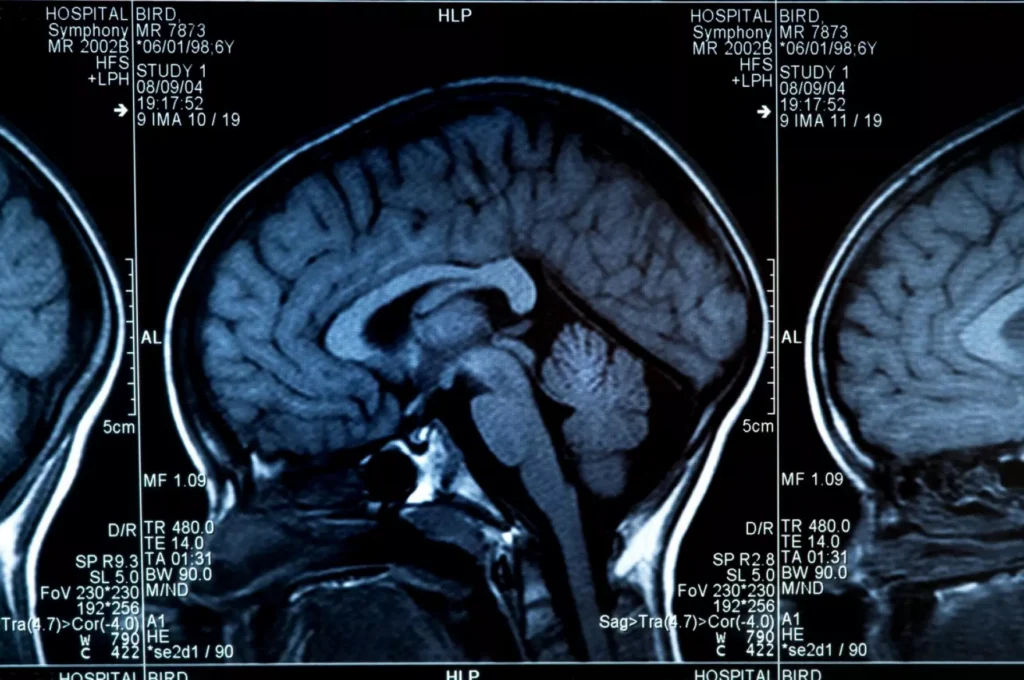

A new paper with the help of a University of Arizona author is offering new insights in how the brain learns and forgets fears.

The research looked at the most common type of cell in the brain called astrocytes, which are star-shaped glial cells that are present throughout the brain. They are not well understood, but they have widely been considered to be support cells that help connect other neurons together.